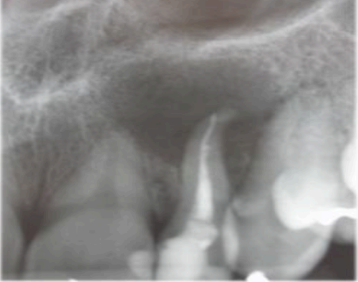

Responda à questão relacionada ao caso clínico a seguir: A paciente A.G.T., 28 anos, sexo feminino, relata história de secreções frequentes e sintomatologia dolorosa à palpação na região do dente 22. Compareceu à clínica cirúrgica com um encaminhamento da endodontia, solicitando avaliação e conduta em relação ao dente 22. Após exame clínico da paciente e avaliação do exame de imagem do dente 22, (que está reproduzido na figura a seguir), ficou evidente a necessidade de tratamento cirúrgico para resolução do quadro clínico apresentado.

Fonte: O autor, 2024.

Em relação ao quadro clínico e a imagem radiográfica acima, analise os itens a seguir.